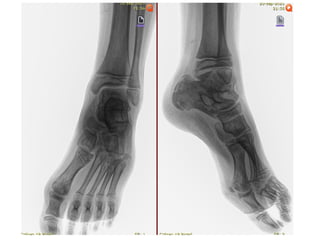

Diagnósticos: FRACTURA DE LA BASE DEL 5TO MTT DE PIE DERECHO (JONES)

Cirugía Proyectada: REDUCCION CERRADA VS ABIERTA FIJACION PERCUTANEA A BASE DE 5TO MTT DE PIE DERECHO

Material OSS Solicitado: NA

NOMBRE:TOLENTINO CRUCES JORGEALEXANDER NSS:3008870166 3M2014OR URGENCIAS A Edad: 10 AÑOS Comorbilidades: NINGUNA Fecha de la lesión: 13/09/25 Mecanismo de lesión: CAIDA DE TRAMPOLIN Laboratorios: DENTRO DE NORMALIDAD Valoraciones: NA Diagnósticos: FRACTURA DE LA BASE DEL 5TO MTT DE PIE DERECHO (JONES) Cirugía Proyectada: REDUCCION CERRADA VS ABIERTA FIJACION PERCUTANEA A BASE DE 5TO MTT DE PIE DERECHO Material OSS Solicitado: NA